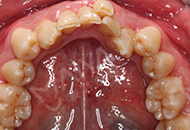

第一次试戴隐形牙套,戴隐形牙套就像戴隐形眼镜一样,刚开始不熟悉,后面就会很好戴,因为是试戴,江洋主任给我示范了好几次,我自己也试着摘戴好几遍,江洋主任真的很耐心,点赞,一共53副,然后一到两周换一副,要带好久啊,不过好期待矫牙后整齐的牙齿!

主任给我做了矫牙方案设计,这是3D隐形矫牙动画预览, 显示牙齿不齐的动画,提前预知矫牙后效果,每一步都可以看到矫牙后的牙齿形态,真的很安全放心。让我矫牙过程中一点都不担心会不会矫正会出现其他问题。